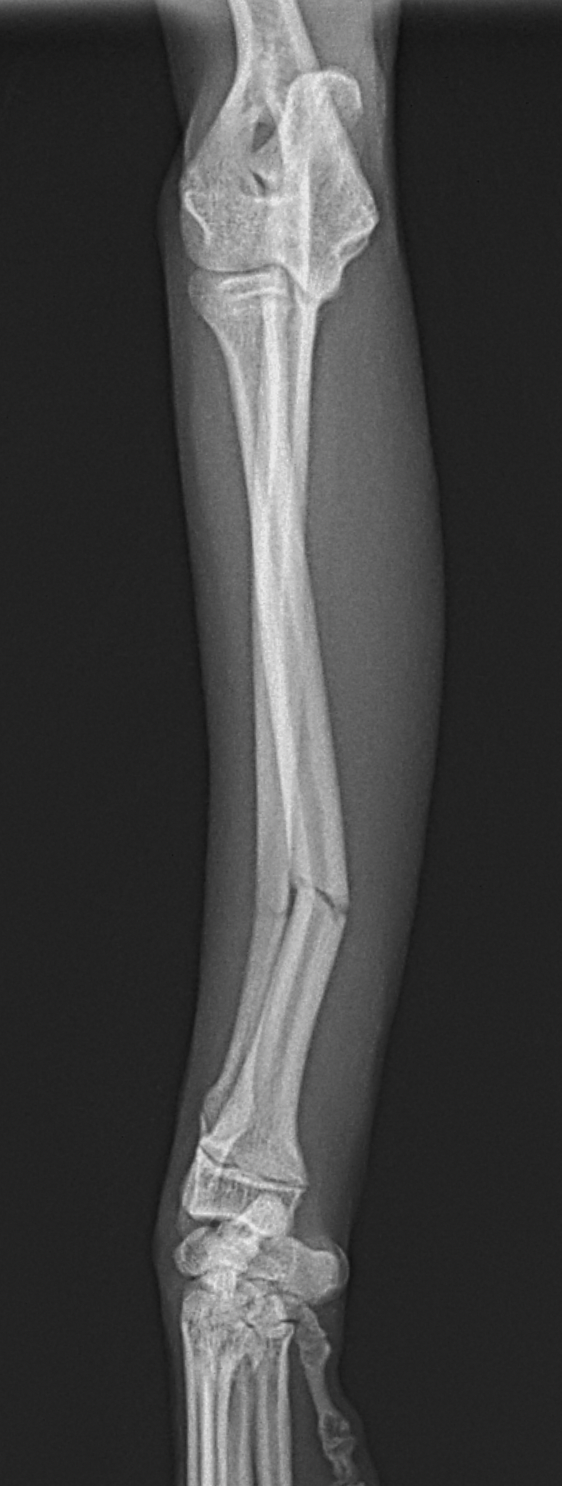

ドッグランで遊んでいた所、他のワンちゃんと接触して橈骨骨折をしたとのことでかかりつけ医より、若い子犬が紹介受診されました。橈骨骨幹部を1.5 Titanium Locking Plateで固定術を行いました。子犬には辛いですがしばらく安静が必要です。